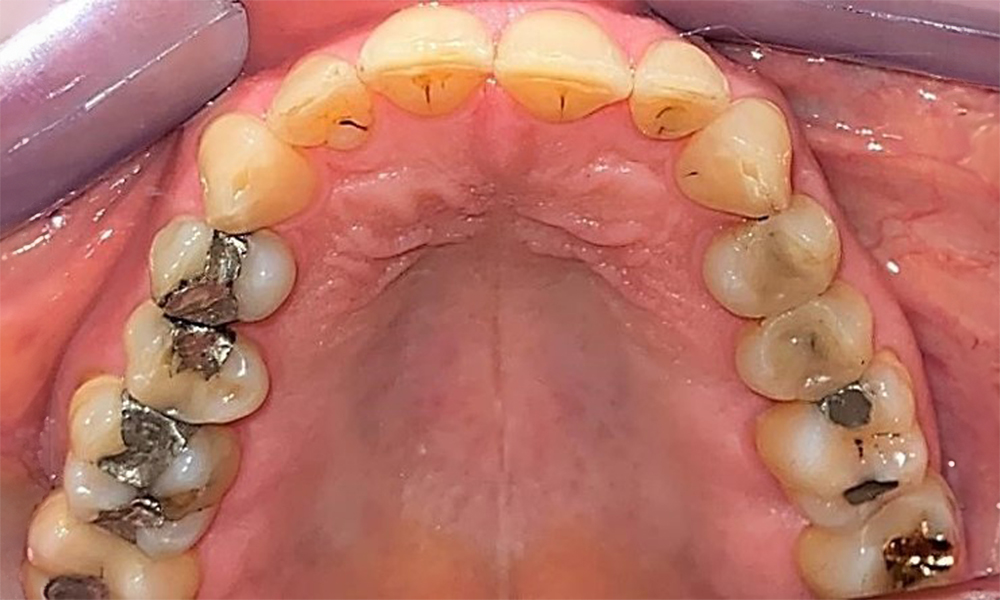

Зъбни резултати

Пациентът има пълно съзъбие с 28 зъба, което включва амалгамни и композитни пломби в областта на моларите и премоларите. На зъб 14 има видима клинична маргинална празнина. Зъб 27 има адекватна златна инкрустация. Налице са и генерализирани атриции и абразии. (фиг. 2, фиг. 3, фиг. 4, фиг. 5, фиг. 6)

Пародонтални резултати

Пациентът е с пародонтит II стадий, степен В (5). Клиничните дълбочини на сондиране от 1 до 3 mm са във физиологичния диапазон. Локализирани дълбочини на сондиране от 5 mm са наблюдавани медиопалатинално на 17 и 27. Налице са генерализирани рецесии от 1 до 3 mm с частична загуба на интердентални папили (фиг. 2, фиг. 3, фиг. 4)